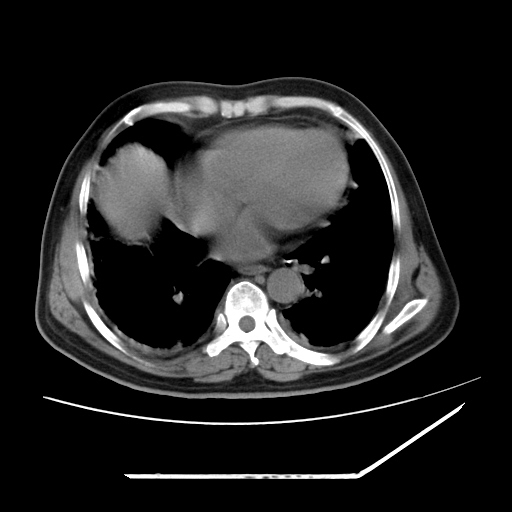

男,57,畏寒,发热

两肺野多发大小不一高密度灶,纵膈内见肿大淋巴结,要考虑转移瘤可能。双侧胸腔少量积液。

1)考虑两肺感染性病变(金黄色葡萄球菌肺炎?);建议抗炎治疗后复查排除其他。2)双侧少量胸腔积液。